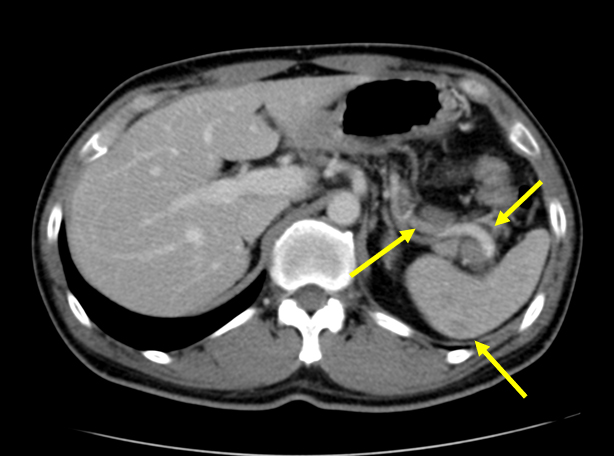

• 脾多発腫瘤、脾門部多発リンパ節腫大

• 肝、脾